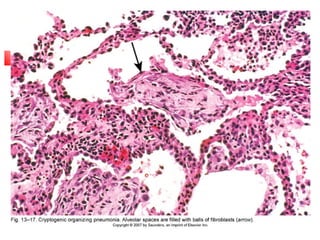

4. Cryptogenic Organizing Pneumonia

 Bronchiolitis Obliterans Organizing Pneumonia (BOOP)

 Many causes (inflammatory, vascular) but mainly cryptogenic

 Polypoid plugs of fibrosis in bronchioles & alveolar ducts & alveoli

 No destruction of lung architecture

 Recovery within 6 months with steroids